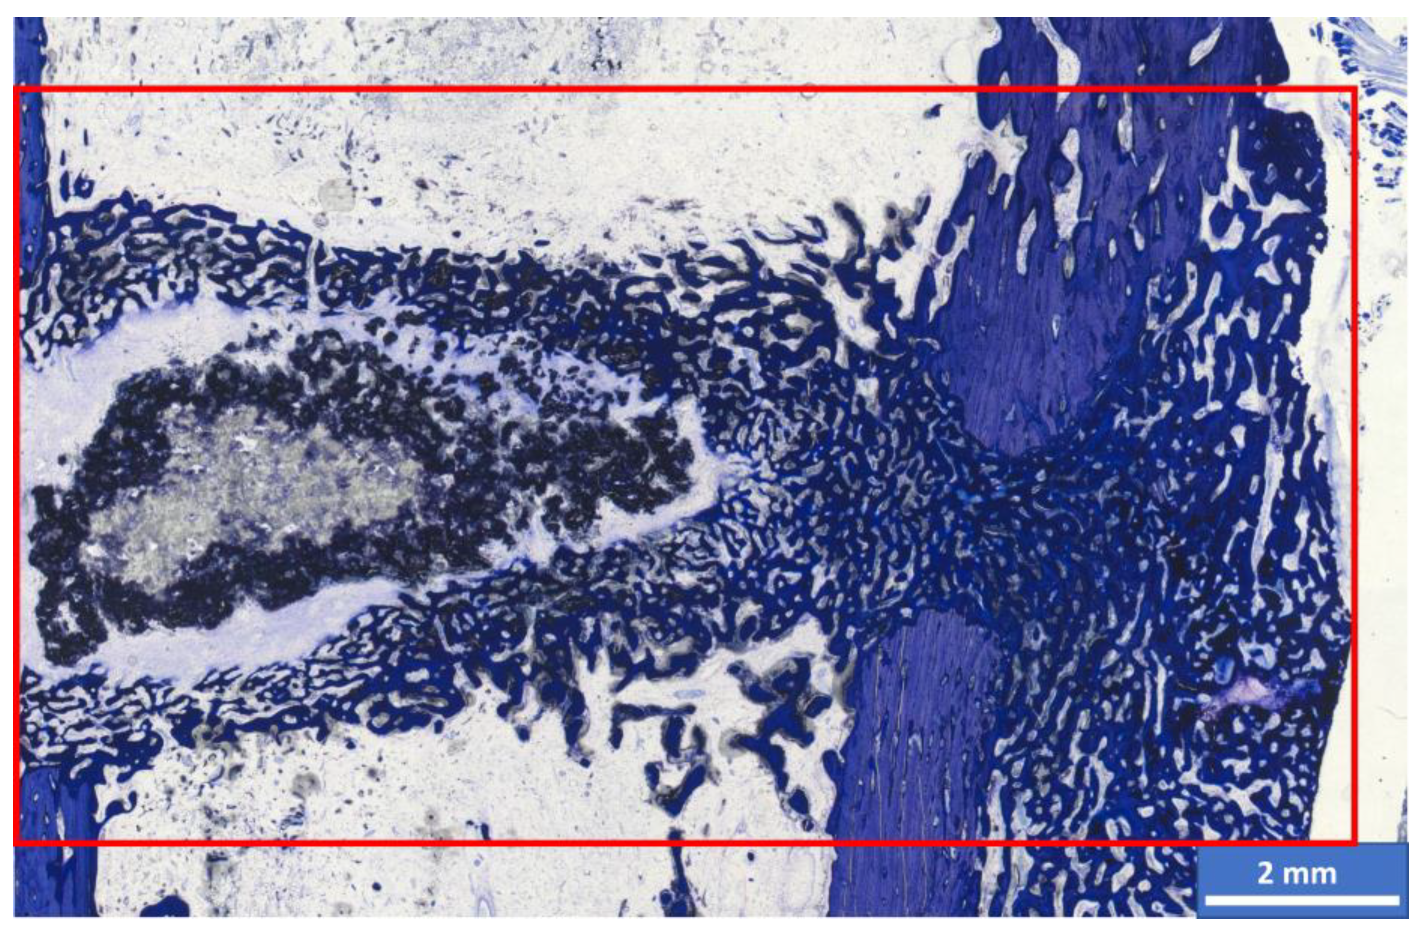

3.6. Histological Examination

3.6.1. Semi-Quantitative Assessment

3.6.2. Histomorphometric Examinations